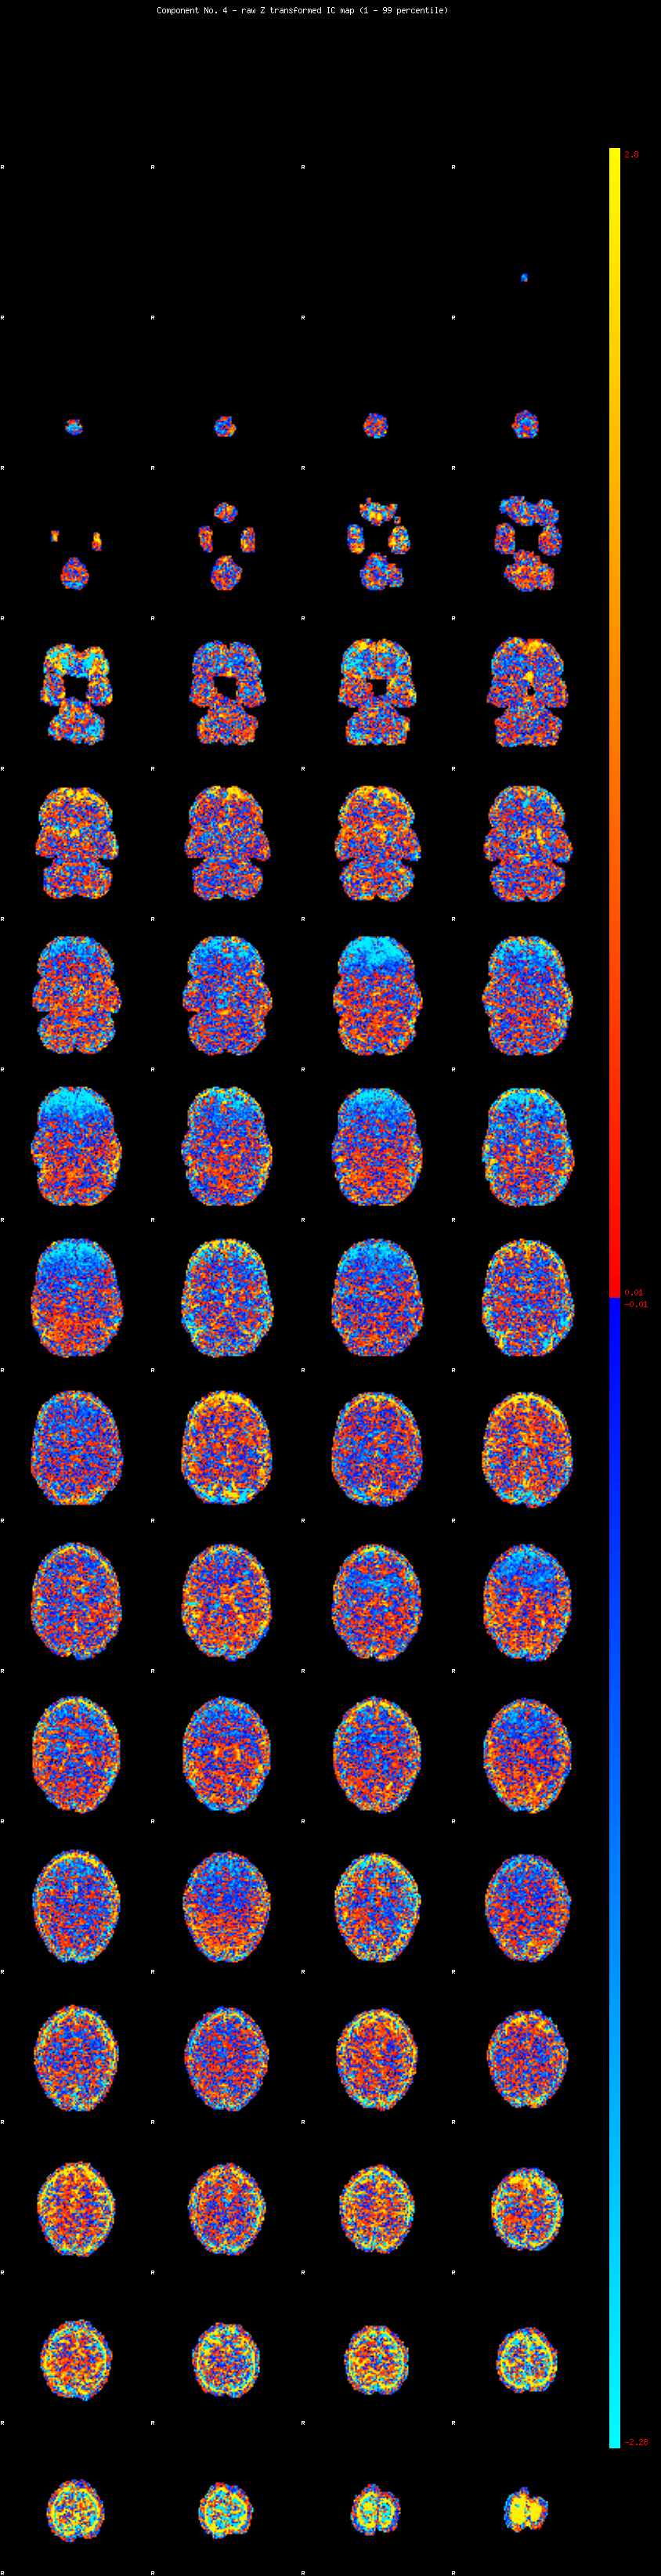

IC_4 Mixture Model fit

Means : 0.000000 3.367761 -2.608594

Vars : 1.000000 5.253775 2.387576

Prop. : 0.865352 0.077052 0.057597